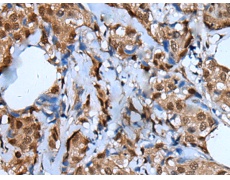

IHC positive control: |

Human breast cancer |